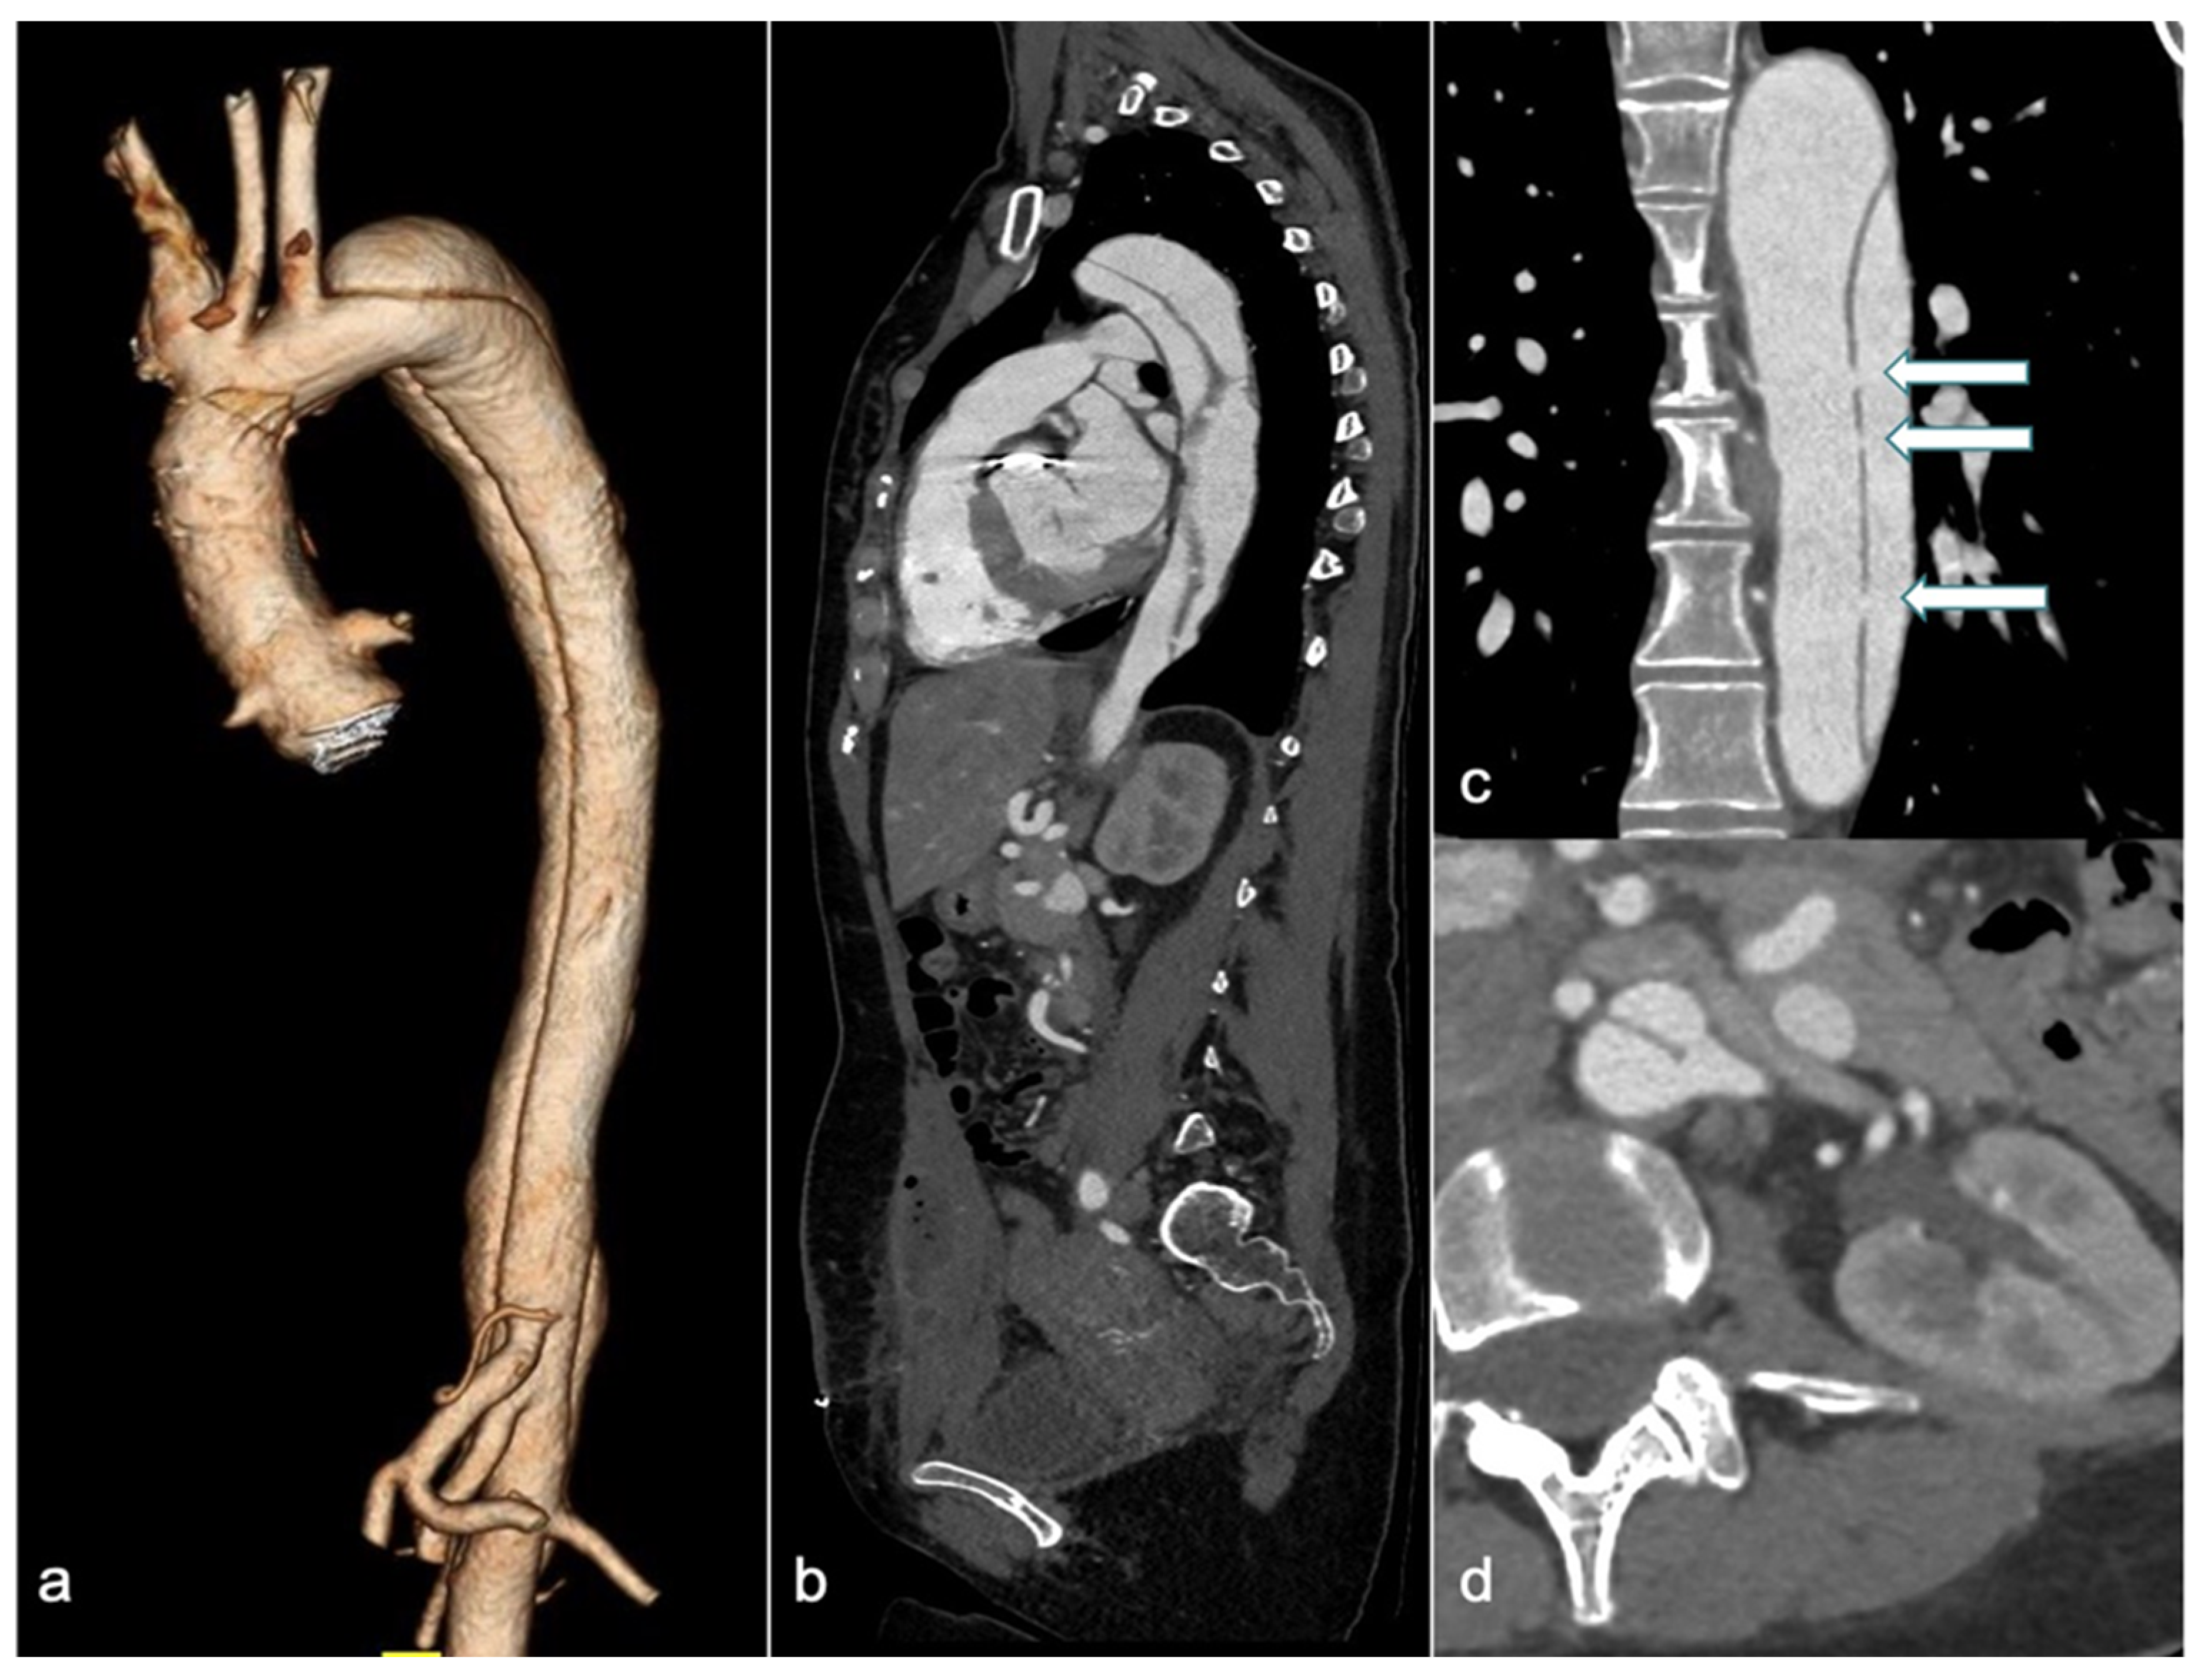

CTA is the first-line imaging modality for diagnosing suspected AD, due to its wide availability, high accuracy, short acquisition time, and ability to provide a comprehensive assessment of the thoracoabdominal aorta (Figure 3) [63].

Figure 3.

A 31-year-old woman with Marfan syndrome and a history of ascending aortic dissection, previously treated with a Bentall procedure, presented with chest pain a few days postpartum. CTA revealed an extension of the dissection into the descending thoracic and abdominal aorta (3D volume rendering in (a), and sagittal and coronal views in (b and c), respectively), with simultaneous enhancement of both the true and false lumens due to multiple intimal fenestrations (arrows in (c)). The sagittal view (b) shows a heterogeneous collection into the rectus abdominis muscles following a recent cesarean section. Axial image (d) reveals the left renal artery originating across both the true and false lumens. CTA: computed tomography angiography and 3D-VR: 3D volume rendering.

However, in pregnant patients, the primary concern is fetal radiation exposure, especially if the fetus is included in the primary radiation field to evaluate the abdominal extent of the AD. Advances in imaging acquisition and processing over the past decade have significantly reduced radiation doses. The effectiveness of ATCM systems and IR techniques in reducing the radiation dose has been well established [64]. In recent years, studies have also demonstrated the feasibility of low tube potential protocols for aortic CTA [65,66]. Fink et al. reported that whole-aortic CTA can be performed with both very low radiation and iodine doses, while maintaining diagnostic image quality, by employing a body mass index (BMI)-adapted protocol [67]. With the introduction and implementation of dual-source CT (DSCT) and DECT technology, the potential savings in radiation and iodine dose for aortic CTA have continuously increased. The use of a DSCT high-pitch protocol for dose reduction has been reported. This protocol decreases the scan time for the entire aorta to approximately 2 s, resulting in a very low radiation dose [68]. Apfaltrer et al. demonstrated that high-pitch CTA of the aorta results in a 45–50% reduction in radiation exposure, along with contrast medium savings, while maintaining vessel attenuation at a diagnostic level [69]. DECT, by comparing two different energy levels, distinguishes materials based on their effective atomic numbers. Virtual non-contrast (VNC) images have been used in AAS imaging protocols for the diagnosis of aortic intramural hematoma (IMH) by subtracting the iodine attenuation from contrast-enhanced scans [70]. This approach demonstrates excellent diagnostic performance while reducing the number of acquisitions and achieving a mean effective dose reduction of 40% [71]. Moreover, various institutions have established protocols to minimize radiation exposure through decision-making algorithms and careful interdisciplinary collaboration. Patel and colleagues designed a specific protocol for patients with suspected AAS who had no prior history of aortic disease and no abdominal or pelvic symptoms. This protocol involved an initial CTA of the chest, which was reviewed by a monitoring radiologist while the patient remained on the scanner table. If no aortic pathology was found, the examination was terminated; conversely, if pathology was detected, a CTA of the abdomen and pelvis was immediately performed. This approach reduced radiation exposure by up to 14.6% [72]. Such strategies are particularly useful for pregnant women, as they can help avoid including the fetus in the primary radiation field whenever possible. Further research is required.